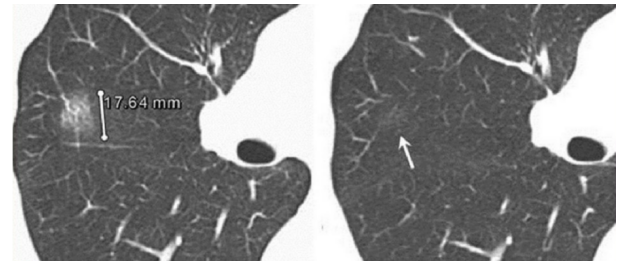

肺结节其实是医学上一类肺影像学表现的统称。其中最常见也是最重要的当属肺磨玻璃影(GGO,ground glass opacity)。GGO在胸部CT表现为密度轻度增高的云雾状淡薄影 / 圆形结节,样子像磨砂玻璃或者云朵的密度一样,所以叫磨玻璃影。(如下图红箭头所示)

图一 肺磨玻璃影

图二 单纯性与混合性GGO影像学表现对比

图四 间隔3个月复查后同一位置GGO消失